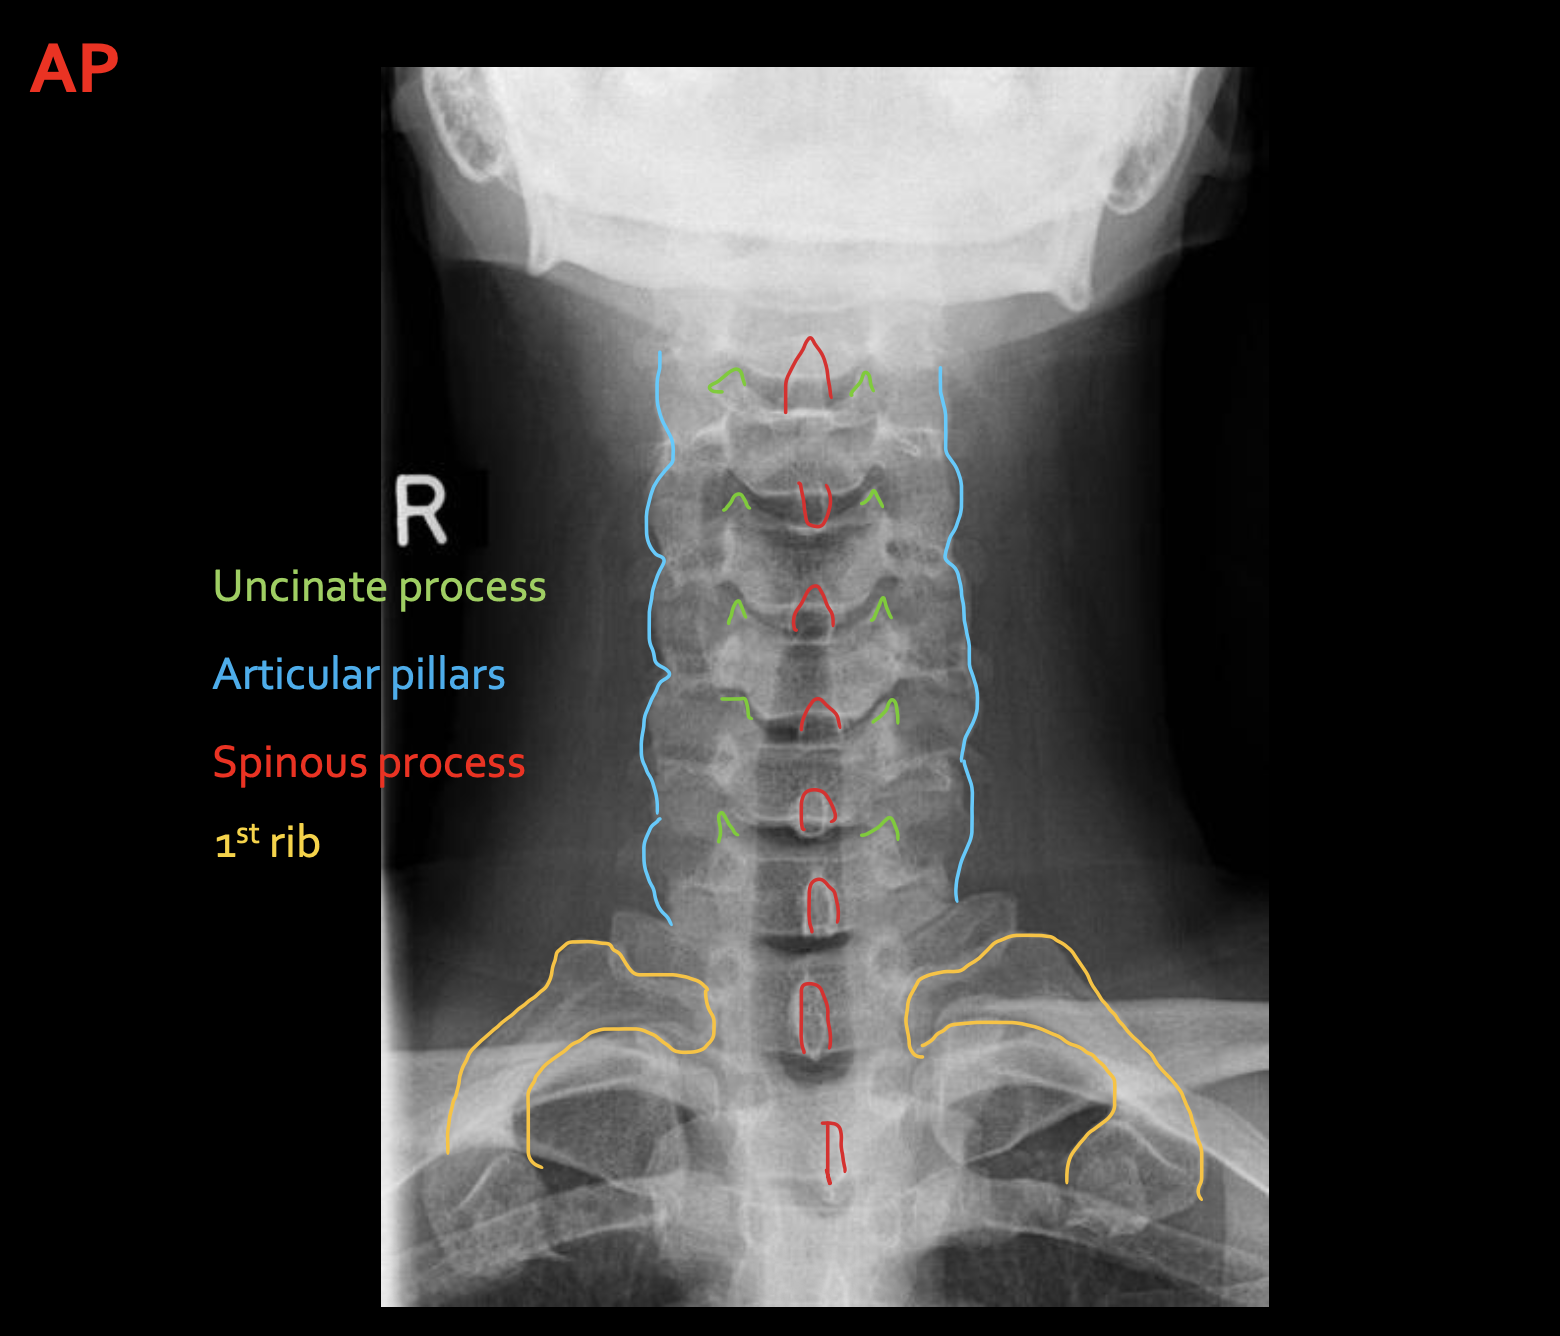

钩突

Uncinate process

关节柱 / 侧块

Articular pillars

棘突

Spinous process

1st rib